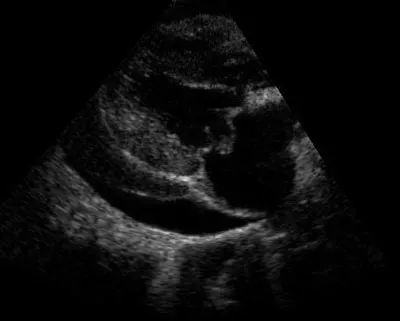

Figure 2: Pericardial effusion diagnosed with TFAST examination